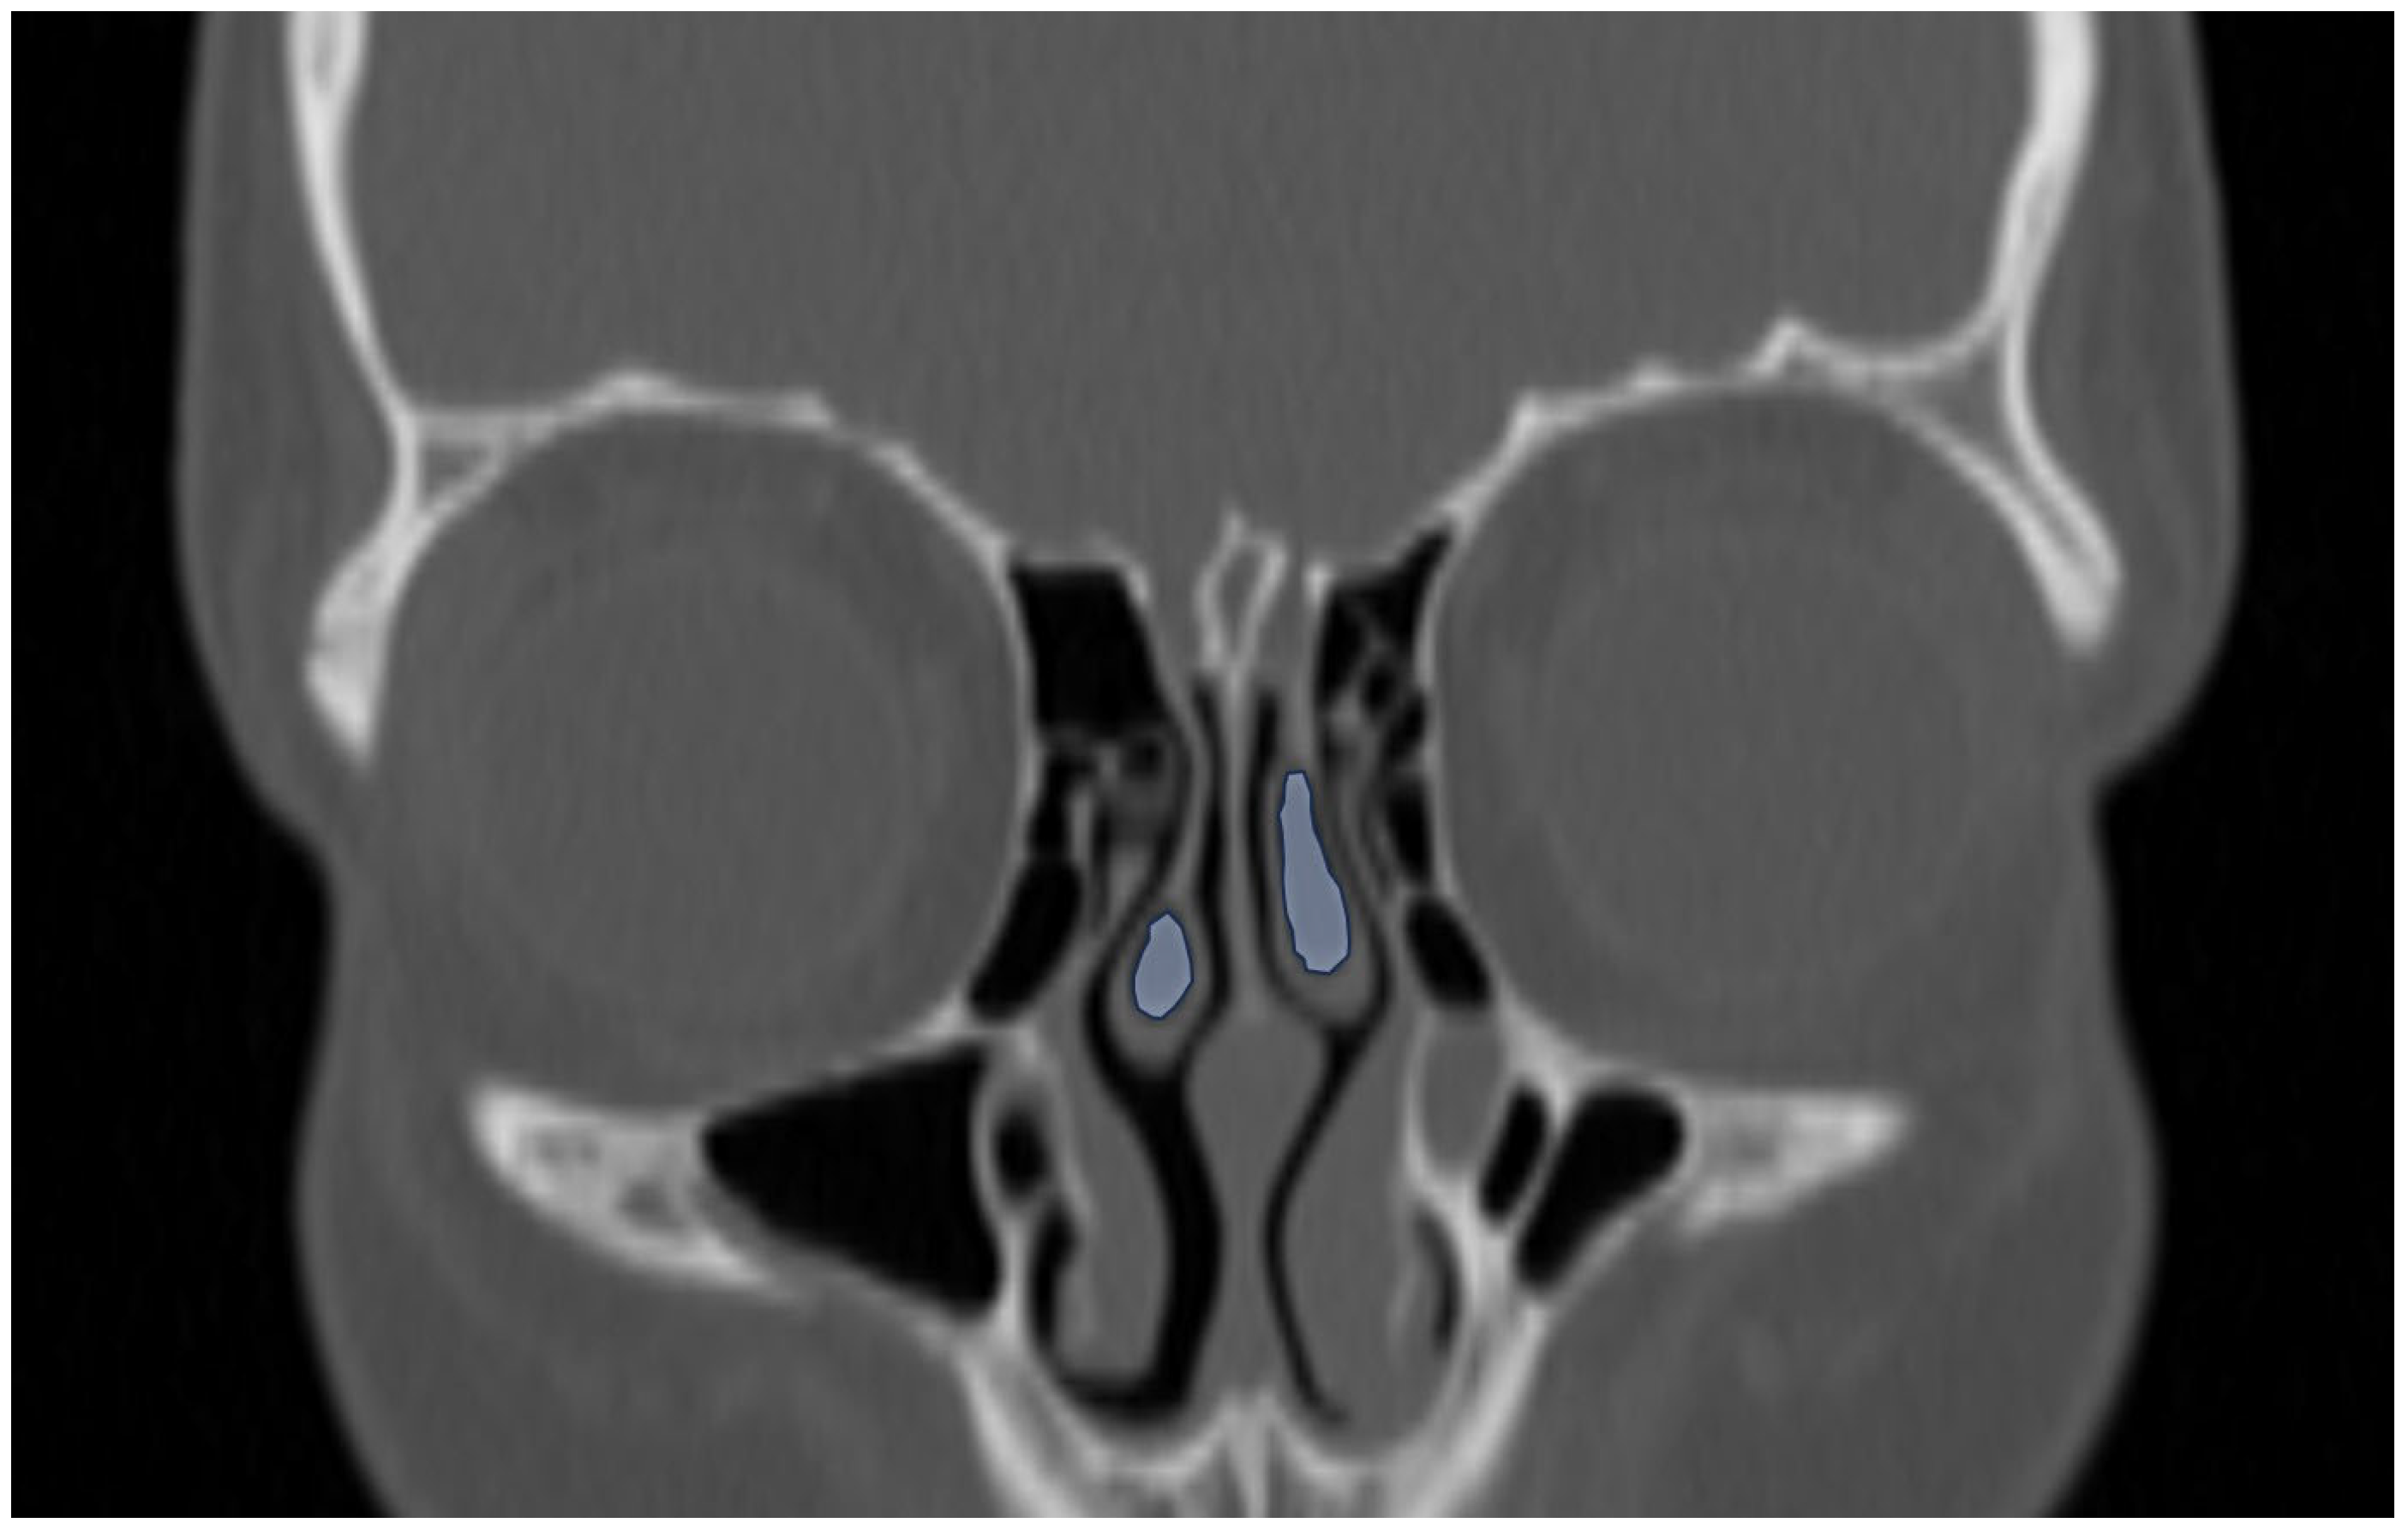

3.2. Sinonasal Variations